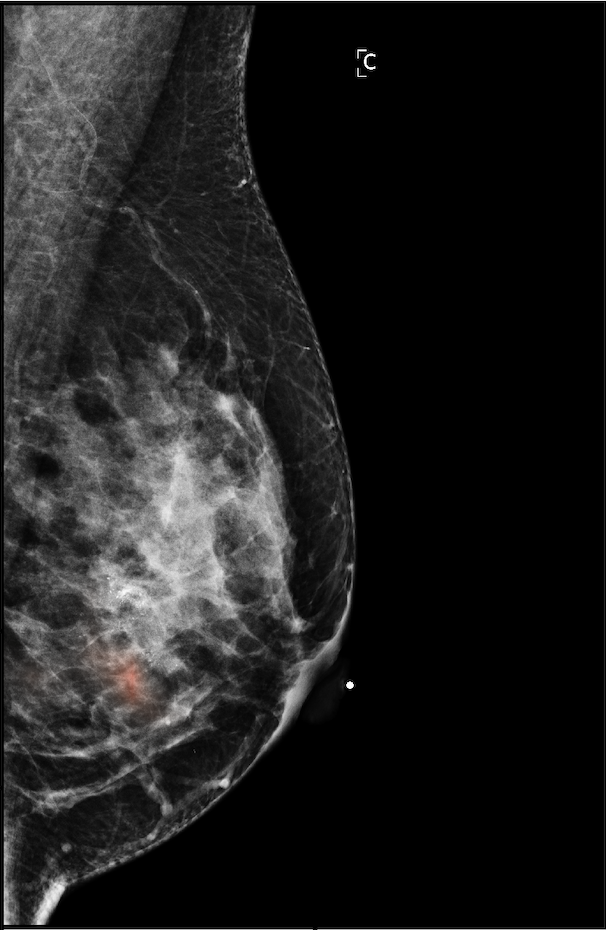

The NYU Breast Cancer Screening Dataset [78] includes 229,426 exams (1,001,093 images) from 141,472 patients.222Our retrospective study was approved by our institutional review board and was compliant with the Health Insurance Portability and Accountability Act. Informed consent was waived. Each exam contains at least four images which correspond to the four standard views used in screening mammography: R-CC (right craniocaudal), L-CC (left craniocaudal), R-MLO (right mediolateral oblique) and L-MLO (left mediolateral oblique). An example is shown in Figure 3.

For all exams matched with biopsies, we asked a group of radiologists (provided with the corresponding pathology reports) to retrospectively indicate the location of the biopsied lesions. This way we obtained the segmentation labels: where if pixel belongs to the benign/malignant findings. An example of such a segmentation is shown in Figure 3. In all experiments (except for experiments in Section 3.6 that assess the benefits of utilizing segmentation labels), segmentation labels are only used for evaluation. We found that, according to the radiologists, approximately of exams were mammographically occult, i.e., the lesions that were biopsied were not visible on mammography, even retrospectively, and were identified using other imaging modalities: ultrasound or MRI.

In Figure 7, we visualize saliency maps for four samples selected from the test set. In the first two examples, the saliency maps are highly activated on the annotated lesions, suggesting that our model is able to detect suspicious lesions without pixel-level supervision. Moreover, the attention is highly concentrated on ROI patches that overlap with the annotated lesions. In the third example, the saliency map for benign findings identifies three abnormalities. Although only the top abnormality was escalated for biopsy and hence annotated by radiologists, the radiologist’s report confirms that the two non-biopsied findings have a high probability of benignity and a low probability of malignancy. In the fourth example, we illustrate a case when there is some level of disagreement between our model and the annotation in the dataset. The malignancy saliency map only highlights part of a large malignant lesion with segmental coarse heterogeneous calcifications. This behavior is related to the design of : a fixed pooling threshold cannot be optimal for all sizes of ROI. The impact of is further studied in 3.6. This example also illustrates that while human experts are asked to annotate the entire lesion, CNNs tend to emphasize only the most informative regions. While no benign lesion is present, the benign saliency map still highlights regions similar to that in the malignancy saliency map, but with a lower probability than the malignancy saliency map. In fact, calcifications with this morphology and distribution can also result from benign pathophysiology [42].

We also assessed how much performance of GMIC could be improved by utilizing pixel-level labels during training. Following [77], we used the pixel-level labels to train a patch-level model which classifies -pixel patches of mammograms, making two predictions: the presence or absence of malignant and benign findings in a given patch. We then apply the patch-level classifier to each full-resolution image in a sliding window fashion to create two heatmaps (illustrated in Figure 11), one containing an estimated probability of a malignant finding for each pixel, and the other containing an estimated probability of a benign finding. In this comparison study, we concatenated the input images with these two heatmaps444The two heatmap channels are only used by the global network . The local network does not use them. to train 30 GMIC-ResNet-18 models (referred as GMIC-ResNet-18-heatmap models) using the hyperparameter optimization setting described in Section 3.3. We reported the test performance of the top-5 GMIC-heatmap models that achieved the highest validation AUC on identifying breasts with malignant lesions. The top-5 GMIC-ResNet-18-heatmap models achieved a mean AUC of / in identifying breasts with malignant/benign lesions, outperforming the vanilla GMIC models ( / ). The ensemble of the top-5 GMIC-ResNet-18-heatmap models achieved an AUC of in identifying breasts with malignant/benign lesions matching the performance of vanilla GMIC models (/). While augmenting GMIC with heatmaps improves its classification performance, the improvement is marginal especially when comparing to the ensemble of models. We conjecture that, for a sufficiently large dataset, image-level labels alone are powerful enough to capture most of the signal, and additional localization information from the pixel-level segmentation labels only slightly improves the performance of GMIC. In fact, sometimes it might even be biasing the model towards ignoring mammographically-occult findings.